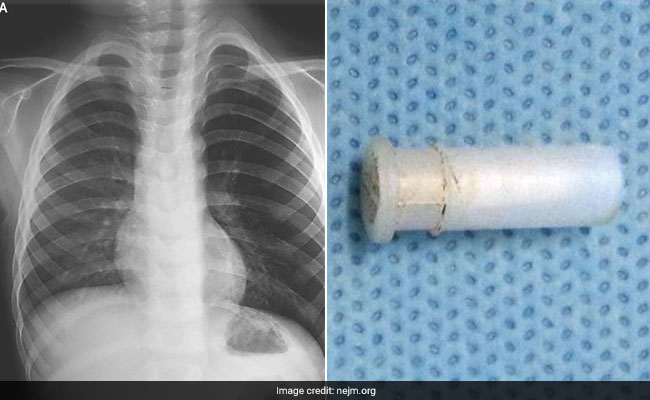

AIIMS Cures 4-Year-Old Of 'Whistling Cough' - He Had Whistle Stuck In Throat

A four-year-old boy who suffered from a strange, whistling cough was cured by doctors from the All India Institute of Medical Sciences, New Delhi. They removed a toy whistle that was lodged in his throat.